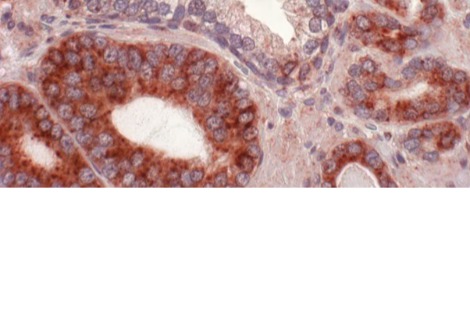

في غضون ذلك، ظلت مستويات بروتين يُسمى CRP مرتفعة. يقول ليز: "يتأثر CRP بعدد من العمليات المختلفة، ومن بينها الالتهاب بالتأكيد، ولكن عوامل مثل التغيرات الهرمونية يمكن أن تؤثر عليه أيضًا". في تحليل آخر، درس الفريق علامات لدى النساء المصابات بتسمم الحمل - وهي حالة أثناء الحمل يمكن أن يسبب فيها ارتفاع ضغط الدم الصداع ومشاكل في الرؤية والولادة المبكرة، ويؤدي إلى مضاعفات مميتة لكل من الأم والطفل إذا تُرك دون علاج. كشف هذا التحليل أن النساء المصابات بتسمم الحمل قبل الحمل لديهن مستويات مرتفعة من شظايا خلايا الدم التي تُسمى الصفائح الدموية وبروتين يُسمى ALT، مقارنةً بمن لم يُصبن بهذه الحالة.

يقول ليز: "لعقود، سادت فكرة أن المشيمة لا تُزرع بشكل صحيح، وإذا لم تُزرع بشكل صحيح، يُعطّل تدفق الدم، وتُطلق هرمونات ومواد تُسبب ارتفاع ضغط دم الأم". ويضيف: "لكن بعض الدراسات تُشير إلى أن وظائف القلب والأوعية الدموية لدى من يُصابون بها تختلف قبل الحمل - وهذه النتائج تُعزز هذه النظرية".